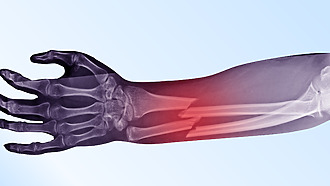

Fracture diagnostics

Diagnosis begins with a physical examination, during which the doctor examines and palpates the affected area.

- An X-ray will provide an accurate picture of the fracture.

- In some cases, magnetic resonance imaging (MRI) or computed tomography (CT) is also used.

- With these examinations, the doctor gets a detailed overview of the condition of the bone and surrounding tissues. [11]

- Most common fracture during working age is a wrist fracture..[13]

- Distal radius fracture is very common, especially in the elderly. This is a type of fracture of the bone that is located in the lower part of the forearm and attaches to the bone of the wrist. It can occur as a result of an injury such as a fall on the wrist. Its healing time can generally take 4-6 weeks. If it requires surgical treatment, the healing time is considerably longer.21]